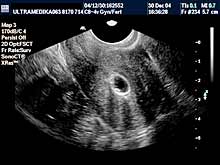

novoformiranih krvnih sudova, ako je došlo do ovulacije. Ova metoda

se naziva folikulometrija. Neadekvatna hormonska aktivnost jajnika

zahteva analize iz krvi radi otkrivanja razloga poremećene funkcije

jajnika. Medikamentna nadoknada, smanjene funkcije jajnika, se

takodje proverava folikulometrijom. Ova stimulacija ovulacije obično

dovodi do ovulacije-sazrevanja jajne ćelije tj određivanja dana u

menstrualnom ciklusu žene kada može doći do začeća. Folikulometrija

određuje vreme započinjanja supstitucione terapije a pregldi

ultrazvukom počinju od 2 ili 5 dana od početka menstruacije (važna

je veličina folikula pre započinjanja terapije da bi stimulacija

bila uspešna).